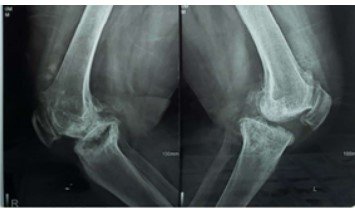

Purpose: Tibial bone defects in total knee arthroplasty (TKA) pose a significant challenge for surgeons, potentially causing improper component balancing. We studied the outcomes of autogenous structural bone grafting

with screws to address medial proximal tibial defects in primary TKA with varus deformity.

2020 and 2024. Patients with uncontained medial proximal tibial defects 10–25 mm in depth who underwent

primary TKA for varus deformity were managed using autogenous structural bone grafts fixed with screws and